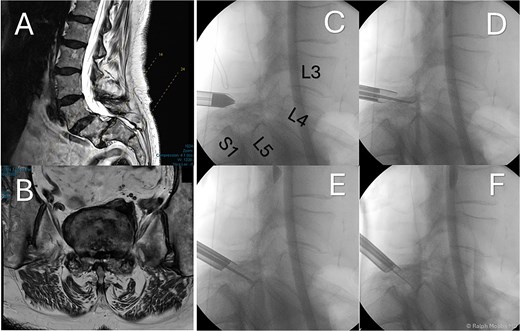

Standing radiographs and magnetic resonance imaging (MRI) demonstrated stable Grade-II L5/S1 degenerative spondylolisthesis with severe bilateral foraminal and lateral-recess stenosis compressing the exiting L5 and traversing S1 roots (Fig. 1). Computed tomography (CT) confirmed intact pars and severe facet arthropathy. Because open decompression/fusion was judged high risk due to significant comorbidities, uniportal full-endoscopic decompression alone under conscious sedation was offered.

Preoperative and intraoperative imaging of case 1. (A) Sagittal T2-weighted MRI demonstrating grade II degenerative spondylolisthesis at the L5/S1 level. (B) Axial T2-weighted MRI. (C–F) intraoperative fluoroscopic views illustrating the placement of the working channel and guidewire.

The operation was performed with patient in the prone position with free abdominal pressure. A skin incision was made positioned just lateral to the midline spinous process at the targeted lumbar interspace. Under fluoroscopic visualization, a series of dilators were advanced through the paraspinal muscles to the lamina, establishing a uniportal working channel (Elliquence, USA) for the endoscopic system with constant irrigation (Fig. 1). Hypertrophied ipsilateral ligamentum flavum and a portion of the ipsilateral facet joint were removed with radiofrequency probe, Kerrison rongeur and grasping forceps, preserving the majority of the facet joint on the approach side.